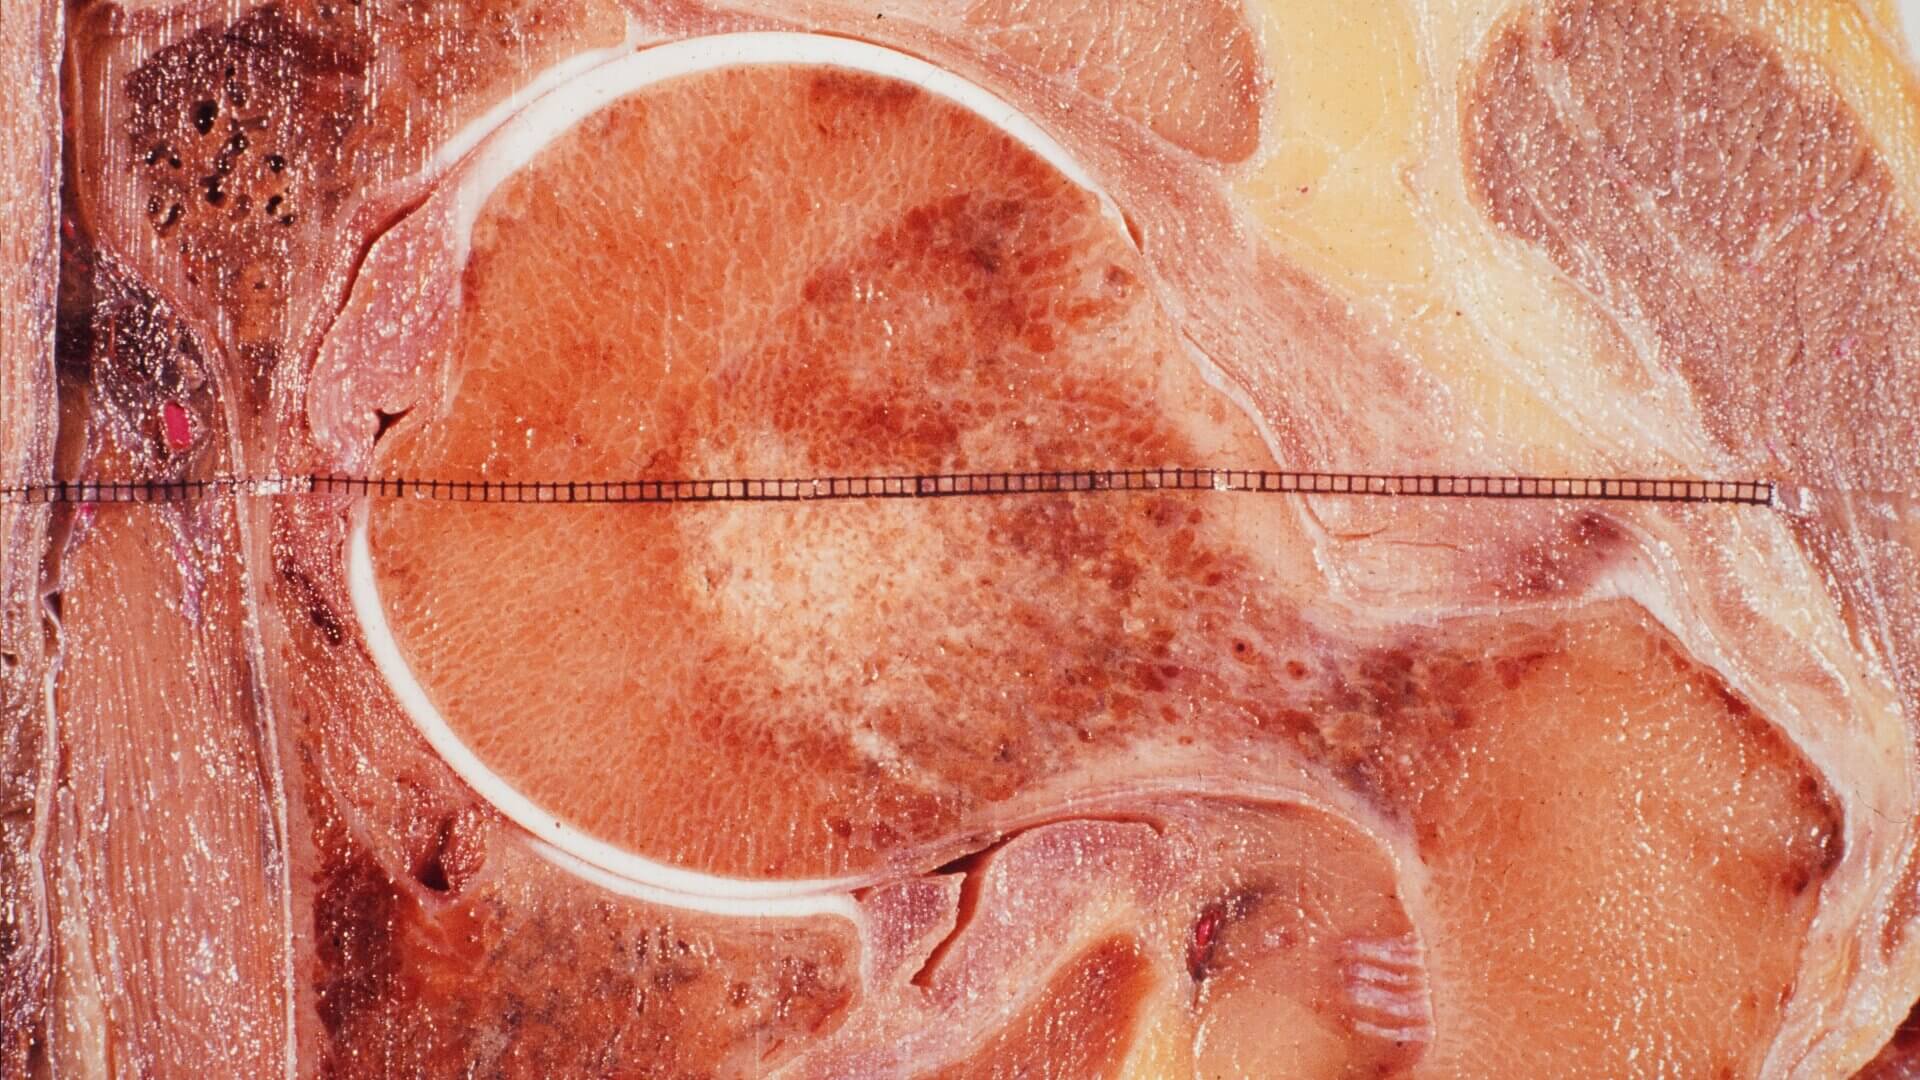

Zu sehen ist eine Detailansicht eines Frontalschnitts des Caput femoris im Acetabulum.